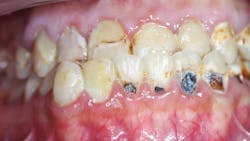

Patient: 24-year-old male with HbSS SCD, renal insufficiency, and frequent vaso-occlusive crises (figure 1)

Chief complaint: Pain, sensitivity, and desire for improved esthetics

Findings

- Rampant caries, pulpal involvement, enamel hypoplasia

- Gingival pallor and mild inflammation

- Facial esthetic concerns and malocclusion